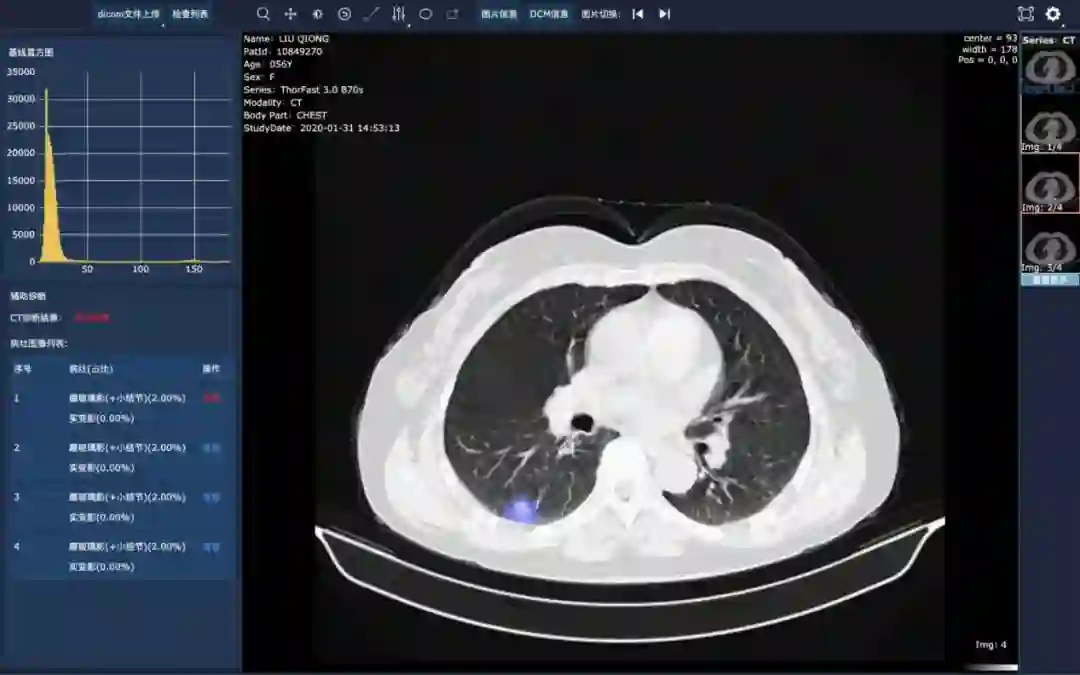

为医院影像科提供一个CT影像辅助诊断工具,该工具可以对COVID-19肺炎、其他病毒性肺炎及细菌性肺炎的六类典型病灶(磨玻璃影、实变、空腔空洞等)自动进行标注,呈现基线直方图,并给出新冠肺炎辅助判读结果预测。

该AI模型使用了图像识别、语义分割、神经网络等关键AI技术,对各影像切片病灶进行精准定位,并实现病灶的像素级识别,准确率超过90%。此外,此系统可以自动计算不同种类病灶的体积占比等量化特征,为影像科医生提供精准判读建议。在此基础上,该模型可以对影像进行影像危重程度评价,在超过4万张CT影像上测试结果显示,模型评价与医生评价的相关性达到0.90以上(p<0.001)。

新冠肺炎影像辅助诊断应用界面

广州中山二院使用实景